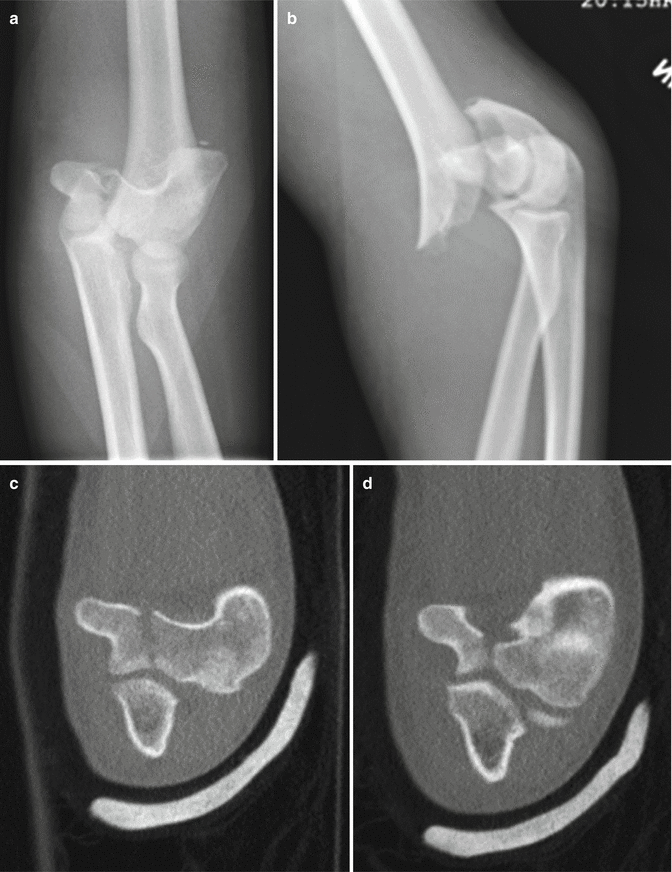

S40S49 Injuries to the shoulder and upper arm ;. Comminuted T condylar fracture of the left distal humerus is noted with intraarticular extension Posterior displacement of the distal fragment is seen in the sagittal plane;. By definition, Tcondylar fractures are intraarticular, distal humerus fractures characterized by a central intercondylar split and extension of the fracture line proximally through both the medial and lateral columns Tcondylar fractures in children are rare elbow fractures and are, perhaps, the most challenging to manage.

Tcondylar fracture is a type of distal humerus fracture Tcondylar fracture in children is rare, with reported incidence of less than 1% of Tcondylar fractures The mean reported age of. Although fractures of the elbow are extremely common in pediatric patients, the Ttype distal humerus fracture is rare and offers unique challenges The mechanism of injury may be similar to the adult counterpart and is usually caused by a fall onto a flexed elbow or from a direct blow Diagnosing these injuries may be difficult. Tcondylar fractures of the distal humerus are very rare in children High degree of suspicion and then further imaging are needed for these types of injuries to be detected Tcondylar fractures can have a high chance of complications Parents should be warned about the likelihood of an unsatisfactory outcome.

Pediatric Tcondylar humerus fractures requiring an open approach may benefit from less invasive approaches such as the triceps split approach where the fracture pattern allows Younger children are more amenable to less invasive means of fracture reduction and fixation If an articular reduction is required, the aggregated literature suggests that the Morrey slide offers equivalent results to the olecranon osteotomy but with fewer approachrelated complications. Blakey CM, Biant LC, Birch R Ischaemia and the of elbow fracture in children analysis of 355 pink, pulseless hand complicating supracondylar fractures, with special reference to supracondylar fractures of the humerus in childhood longterm humerus fractures. With mild lateral/valgus displacement and rotation is noted in the coronal plane No radial or ulnar fracture is notedSoft tissue swelling is noted around the elbow.